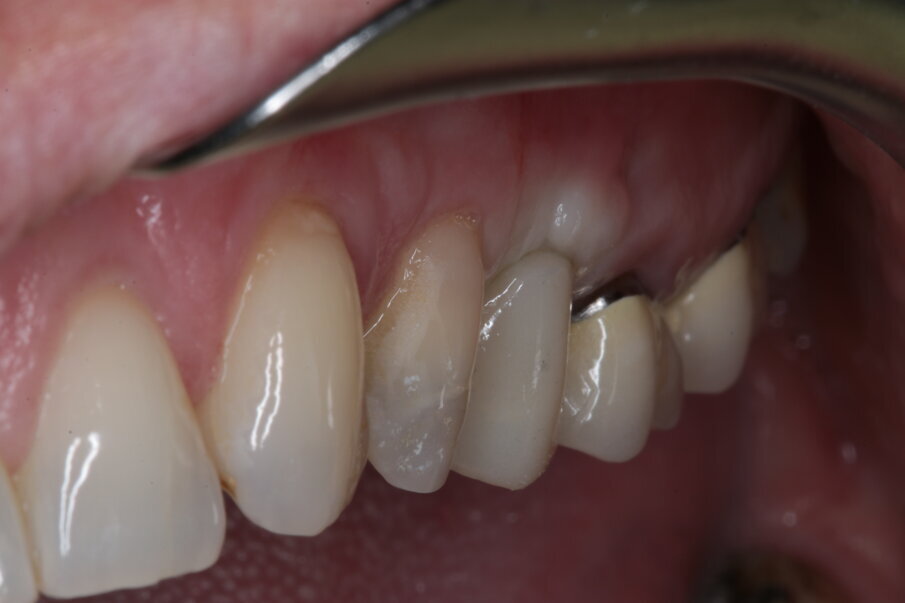

Nelle prime fasi questo avrà un profilo ovviamente non compatibile con quello di un restauro definitivo, ma molto utile per ottenere una compressione sul connettivo ormai maturo che migrerà verso vestibolare e verso coronale (Figg. 18-21). Dopo tre mesi, nei quali il provvisorio viene progressivamente ridotto nella sua componente vestibolare seguendo la risposta dei tessuti, e la paziente costantemente monitorata nel mantenimento della sua igiene orale, viene rilevata l’impronta tramite scanner ottico (Figg. 22-24) e consegnato il definitivo avvitato in zirconia, con un profilo ancora più ridotto e a questo punto ideale anche per il mantenimento igienico (Figg. 25-28).